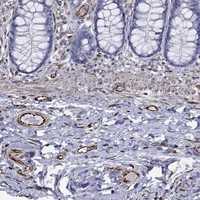

Immunohistochemical staining of human colon shows strong membranous positivity in endothelial cells.